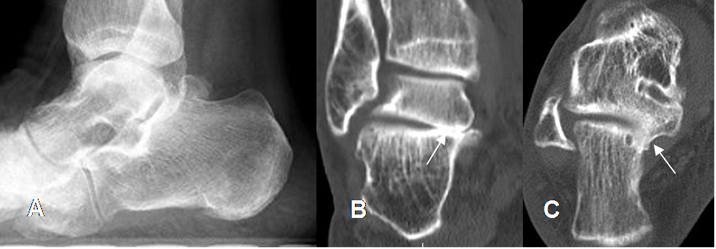

Fig 135 A. Coalición del tarso.

A: Rx lateral. Pie plano y visualización de os trigonum.

B: TAC reconstrucción coronal y B: TAC axial. Coalición talocalcánea ósea interna.